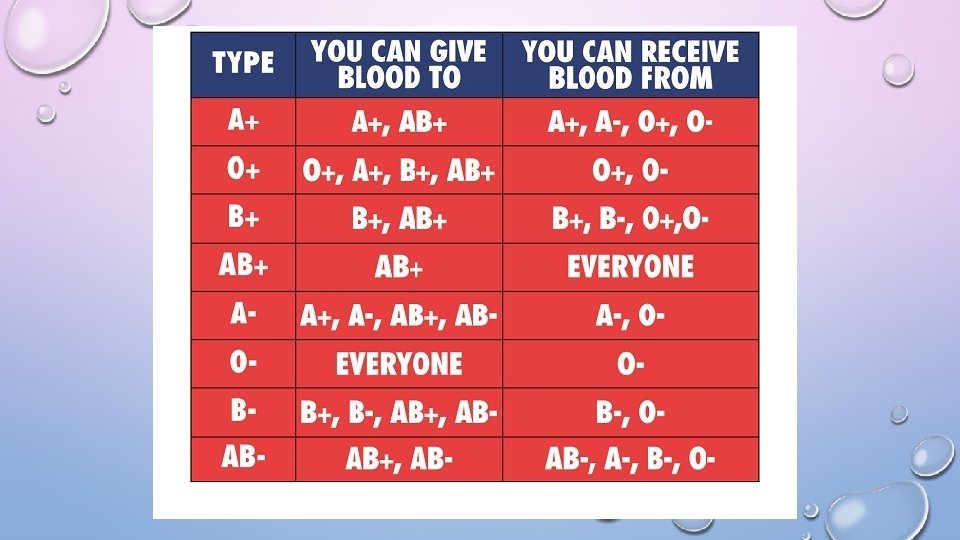

BLOOD PERCENTAGES ON PLANET (APPROX. ) • O+ 38% O- 7% = 46% • A+ 32% A- 6% = 38% • B+ 9% B- 1% = 11% • AB+ 3% AB-. 7% = 4% TRANSFUSIONS • TYPE O UNIVERSAL DONOR • TYPE AB UNIVERSAL RECIPIENT

RH FACTOR • RHESUS MONKEY EITHER YOU HAVE THE PROTEIN (+) OR NOT (-)